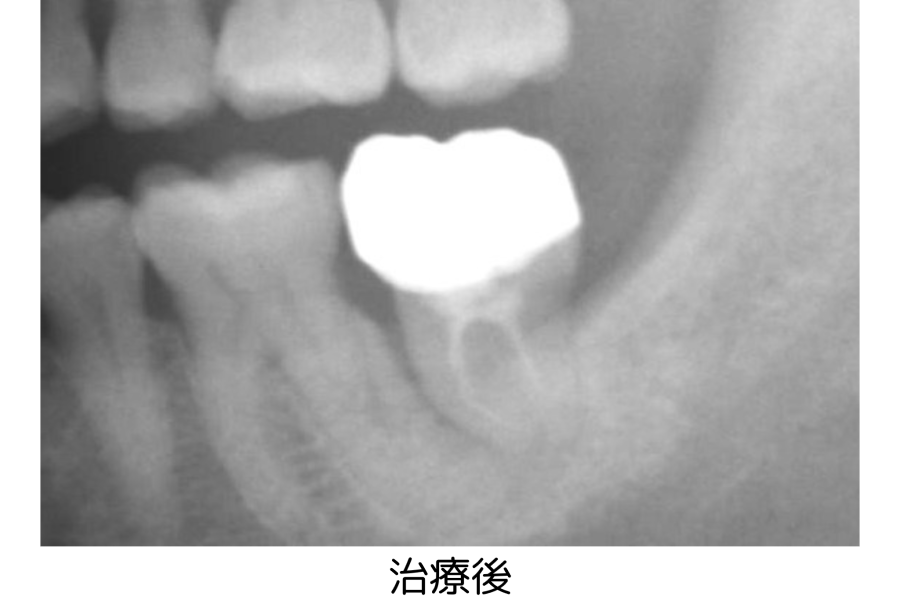

CASE 1

年齢・性別 57歳・男性

主訴 歯の揺れが気になる

左下7

治療日数 5ヶ月

治療費 合計 195,800円

右下8を左下7へ移植

歯の移植、再生治療、根管治療 132,000円

仮歯、ジルコニアクラウン 63,800円

(2023年5月現在)

治療内容 歯の移植

治療方針 左下7に歯の揺れがあり気になるとのことで受診されました。

左下7が歯周病の進行があり歯を残すことができないため、右下の親知らずを移植しました。

担当者所見 この方は、喫煙もされないことと生活歯だったので歯の移植をすることが可能となりました。

歯の状態によっては、移植ができないこともあります。